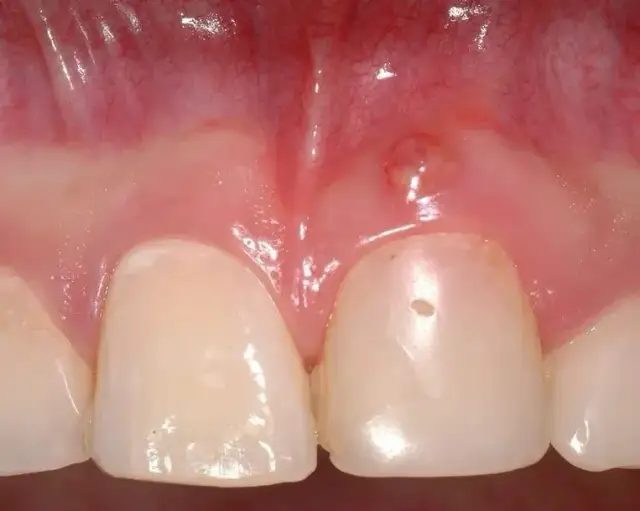

Czy zapalenie dziąseł jest zaraźliwe? Poznaj różnicę między przenoszeniem bakterii a chorobą. Dowiedz się, jak skutecznie chronić siebie i bliskich!

Opuchnięte dziąsła? Poznaj najczęstsze przyczyny, objawy i skuteczne metody leczenia. Sprawdź, jak sobie pomóc i kiedy iść do dentysty.

Ropa w dziąśle? Sprawdź domowe sposoby na ulgę i leki bez recepty. Dowiedz się, czego unikać i kiedy pilnie do dentysty, by uniknąć powikłań.

Opuchnięte dziąsła? Odkryj sprawdzone domowe sposoby na szybką ulgę i dowiedz się, kiedy konieczna jest wizyta u dentysty. Zadbaj o zdrowie jamy ustnej!